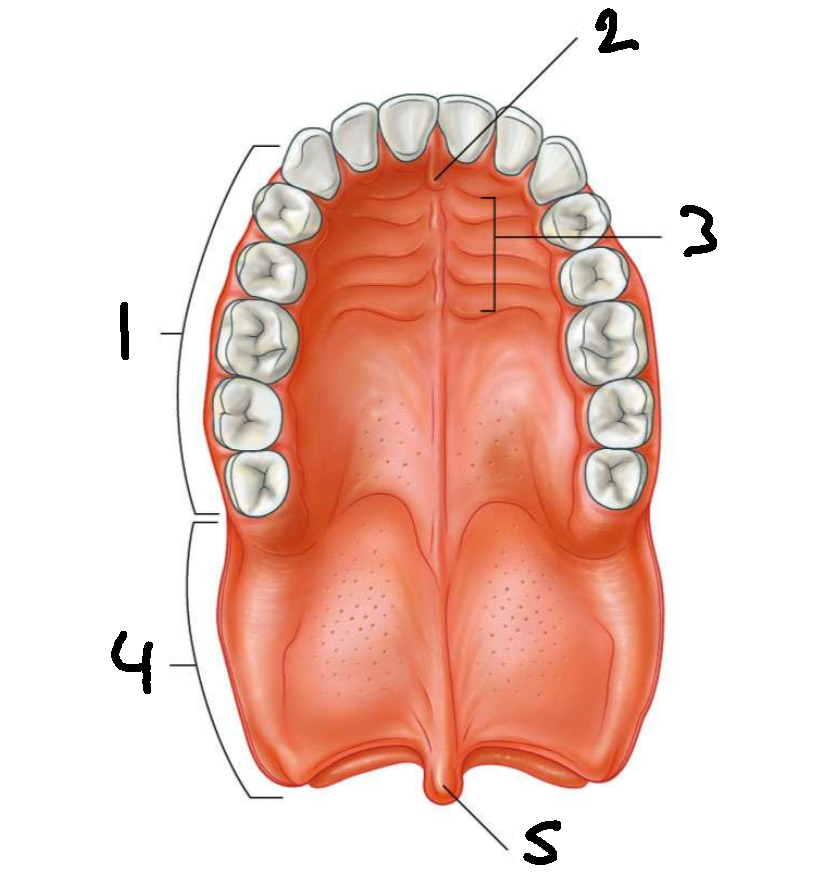

What is 1?

hard palate

What is 2?

incisive papilla

What is 3?

palatine rugae

What is 4?

soft palate

What is 5?

uvula